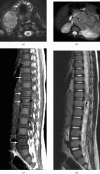

Neuroblastoma is one of the most common malignant neoplasms in childhood. The most common clinical presentation of this tumour is abdominal mass. However, affected children may have various clinical presentations as a result of disseminated metastatic disease or associated paraneoplastic syndromes at the time of diagnosis. In this article we have outlined the imaging findings in seven patients with "extra-abdominal" presentation of neuroblastoma and the pitfalls in making the correct diagnosis. The purpose of this pictorial review is to alert the general radiologist to the possible presentations of this common childhood malignancy to derive early detection and diagnosis.